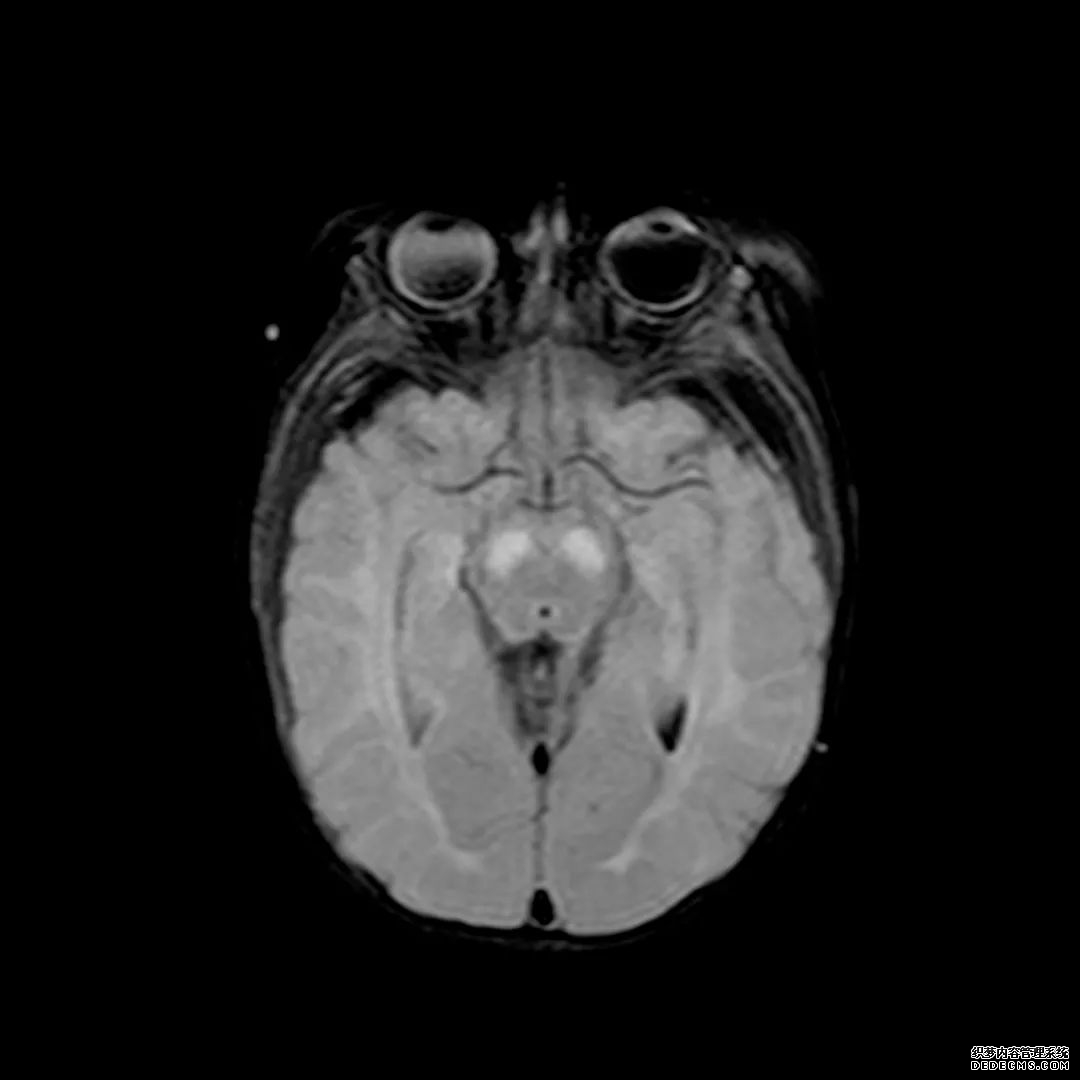

脑MRI显示尾状核、扁豆状核和脑梗头部T2/FLAIR呈双侧对称异常高信号。扩散限制涉及这些区域,其特征是扩散加权DWI(B-1000)上的高强度,ADC图上相应的减弱强度。

印象:通过将这些成像模式与临床和实验室检查结果相结合,就有可能得出低血糖性脑病。

影像影响内囊后肢、大脑皮层(特别是枕叶和岛叶)、海马和基底节区,常是双边对称性的。